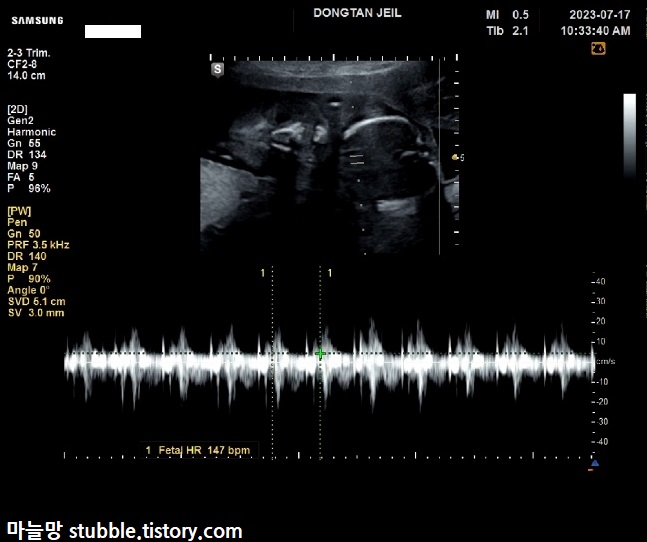

이어서 19주 4일차의 우렁찬 심장소리를 들었어요.

147bpm이 나왔어요.